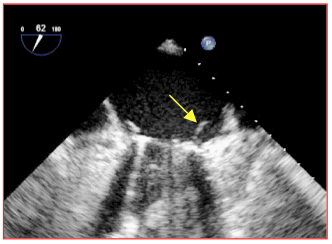

La valve doit être immobile par rapport aux structures qui l’entourent. Un mouvement de bascule avec chaque cycle cardiaque laisse supposer un descellement et une déhiscence. En position mitrale, toutefois, la conservation de l'appareil sous-valvulaire et de la base des feuillets peut donner une certaine mobilité à la prothèse [30]. Une cavité péri-annulaire sans écho fait penser à une déhiscence, à un abcès ou à une fistule [15]. Des éléments de l’appareil sous-valvulaire, une thrombose ou un pannus inflammatoire peuvent bloquer une ailette ; le mouvement d’ouverture est alors asymétrique et la fermeture incomplète (Vidéos). Le pannus est typiquement plus échogène que le thrombus. Les valves biologiques ont tendance à dégénérer à partir d’une douzaine d’années ; elle se fibrosent et se calcifient, ce qui entraîne une sténose, ou elles se fragmentent et se déchirent, ce qui occasionne des fuites (Vidéos). Après remplacement valvulaire mitral (RVM), il est fréquent de déceler dans l’OG des filaments de fibrine (fibrin strands), qui apparaissent comme des structures filiformes peu échogènes de quelques millimètres qui ondulent dans le flux au voisinage de la prothèse (Figure 26.148). Après remplacement valvulaire aortique (RVA), on en rencontre quelquefois dans la CCVG. Ces éléments sont probablement constitués de collagène; ils sont attachés à la face d'amont de la valve et sont plus fréquents sur les prothèses mécaniques que sur les bioprothèses (27% versus 8%) [16,18]. Les fils de suture s’en différencient pas leur rigidité et leur très forte échogénicité (Vidéo). Après un RVA, la racine de l'aorte est en général épaissie et déformée par un hématome qui se fibrose ultérieurement, mais ce manchon peut faire croire à un abcès péri-aortique. Il se résorbe en 3-6 mois.

Figure 26.148 : Filament de fibrine (flèche) sur une prohèse mécanique en position mitrale.